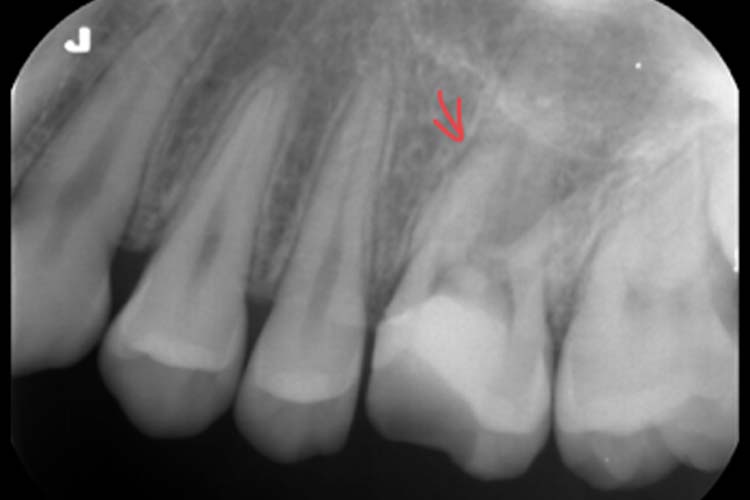

初診時デンタル所見

根の先まで根管充填がなされていない根管がある。

ファイル様不透過像を認める←根管充填材とは写り方が違う。

左上6番 慢性根尖性歯周炎・近心頬側根管に根管内異物